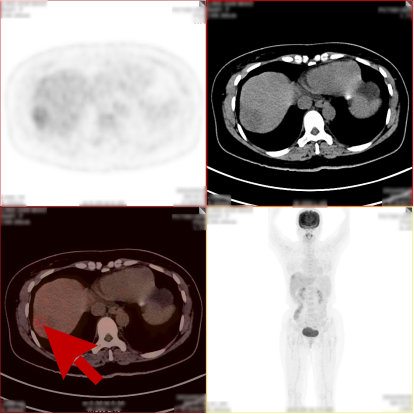

病史:女,48岁,无明显不适,健康查体,无特殊病史及手术史。乙肝大三阳,AFP:380.21ng/mL,CA199:33.24U/ml,CA125、CA153、CA724、 CEA(-)。

PET/CT检查所见

1、肝 S8 段见 1 个稍低密度软组织肿块,病灶内部分组织代谢增高,考虑肝细胞肝癌;

2、肝 S8 段另见 1 个稍低密度结节,代谢轻度增高,考虑为小肝癌或肝内子灶形成,该压迫相邻肝中静脉。

PET/CT活检病理:原发性肝癌